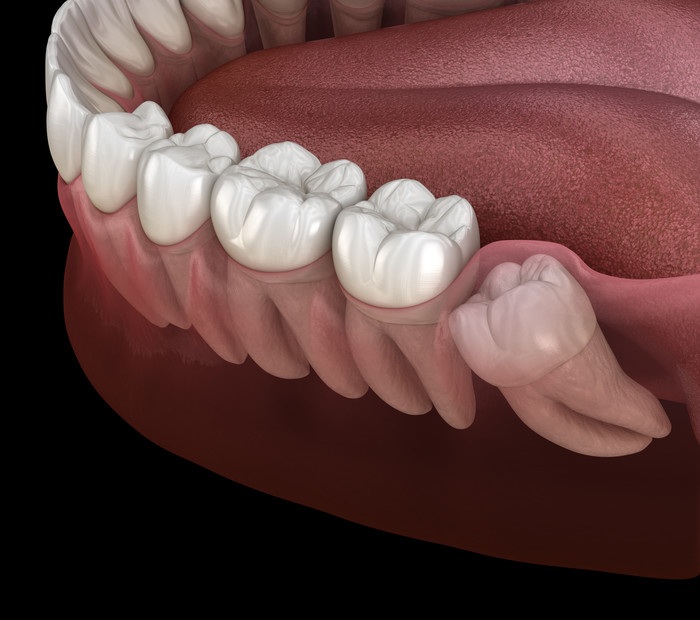

사랑니는 우리 입속에 가장 뒤에 난 어금니를 말하며, 전문용어로 설명해 드리면 제3대구치라고 하며 얼굴을 중심으로 좌우로 8번째 자리하고 있는 치아를 말합니다. 사랑니는 사춘기 이후에 자란다고 합니다. 사춘기에는 여러 가지 감정을 느끼게 되고 그 감정 중 하나가 사랑이라는 감정이지요. 그래서 이 치아를 사랑니라고 부른다고 합니다.

치과 치료를 하면 알 수 있는 것이 치아는 함부로 뽑지 않습니다. 정말 최대한 살려보고 그래도 안 되면 뽑아서 임플란트 등으로 빈자리를 채웁니다. 사랑니는 다른 치아들과 달리 발치를 해야 할 때도 있습니다. 잘 자란 사랑니는 특별한 문제를 일으키지 않아 뽑지 않아도 됩니다. 하지만 대부분의 사랑니는 말썽을 부립니다. 출혈, 염증, 통증 및 악취, 충치 들 여러 가지 문제를 일으킬 확률이 높기 때문에 뽑아야 합니다.